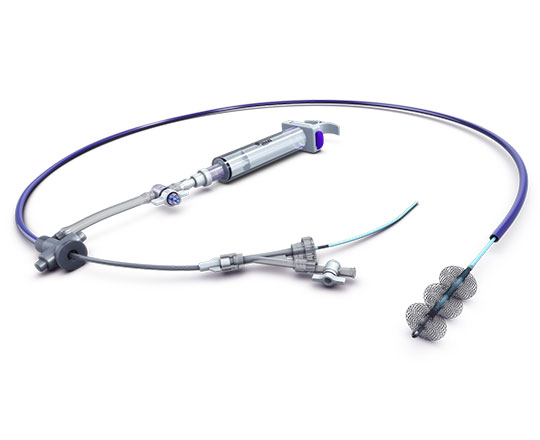

True Flow (Bard, EEUU) es un balón de valvuloplastia que permite el flujo a su través mientras está inflado. Su recubrimiento exterior está compuesto por un tejido de fibras que evita el deslizamiento del balón al abrirse sobre los velos valvulares, por lo que no se necesita estimular el corazón con marcapasos. Este tejido esta formado por poliuretano de alto peso molecular, poliéster y fibras de aramida (componente estructural del Kevlar) que posee una baja distensibilidad y alta resistencia a la rotura. El interior del balón tiene 8 globos de pequeño diámetro en el perímetro del balón principal, y deja un espacio entre ellos por donde fluye la sangre. El dispositivo mide 3,5 cm de largo y está disponible en seis tamaños, con diámetros que van de los 18 a los 26 mm. Los más pequeños son compatibles con un introductor de 11 French y el más grande con introductor de 16 French.